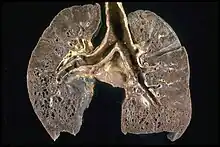

Respiratory tract

Localization to the lungs is by far the most common manifestation of sarcoidosis.[27] At least 90% of those affected experience lung involvement.[28] Overall, about 50% develop permanent pulmonary abnormalities, and 5 to 15% have progressive fibrosis of the lung parenchyma. Sarcoidosis of the lung is primarily an interstitial lung disease in which the inflammatory process involves the alveoli, small bronchi, and small blood vessels.[29] In acute and subacute cases, physical examination usually reveals dry crackles.[28] At least 5% of cases include pulmonary arterial hypertension.[28][30] The upper respiratory tract (including the larynx, pharynx, and sinuses) may be affected, which occurs in between 5 and 10% of cases.[31]

The four stages of pulmonary involvement are based on radiological stage of the disease, which is helpful in prognosis:[32]

- Stage I: bilateral hilar lymphadenopathy (BHL) alone

- Stage II: BHL with pulmonary infiltrates

- Stage III: pulmonary infiltrates without BHL

- Stage IV: fibrosis

Use of the Scadding scale only provides general information regarding the prognosis of the pulmonary disease over time. Caution is recommended, as it only shows a general relation with physiological markers of the disease and the variation is such that it has limited applicability in individual assessments, including treatment decisions.[12]